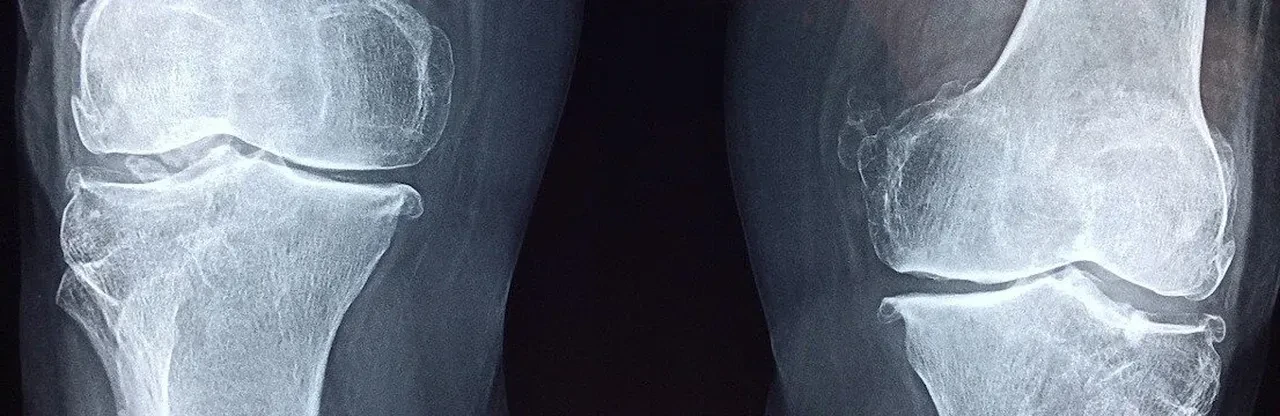

Toplumda yaygın bir inanış, dizlerden gelen sesin eklemde hasar ya da erken dönem kireçlenme (osteoartrit) belirtisi olduğudur. Ancak bu doğru değil. Nitekim ağrısı olmayan ve hiç diz yaralanması geçirmemiş kişilerin yüzde 36’sında da diz krepitusu görülüyor.

Öte yandan, kireçlenmesi olan kişilerde bu ses çok daha sık rastlanıyor. Örneğin osteoartrit hastalarının yüzde 81’inde dizlerde ses olduğu saptanmış. Buna rağmen yapılan uzun dönemli çalışmalarda, yalnızca diz sesi olan kişilerin büyük bölümünde ilerleyen yıllarda eklem hastalığı gelişmediği ortaya kondu.